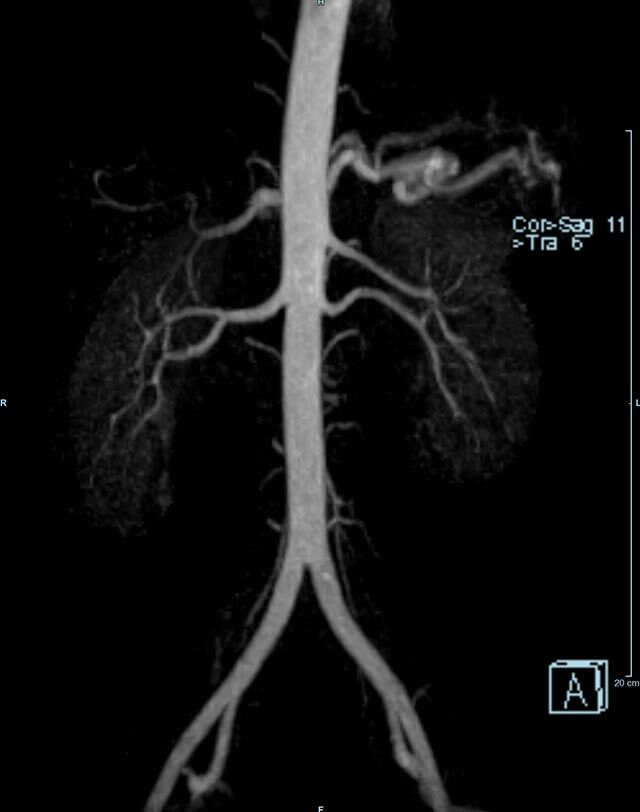

Aorta

• Bauchgefäße

• Erfassung und Verlaufskontrolle bei arteriellen Aneurysmen (Aussackungen der Arterien), vor allem der Bauchaorta

• Darstellung von Gefäßengen an Nierenarterien, Baucharterien und Becken-/Beinarterien

MR-Angiografie (MRA)

Ganzkörper Angiographie mit Kontrastmittel

• MR-Angiographie mit Kontrastmittel

• Erfassung arterieller und venöser Gefäße/Bypässe aller Körperregionen mit 3D-Rekonstruktion

• je nach klinischer Fragestellung zeitaufgelöste MR-Angiographie (4D-MRA) z.B. bei Frage arteriovenöse Fistel/ Shunt oder Darstellung Unterschenkelarterien vor geplanter Bypassoperation.